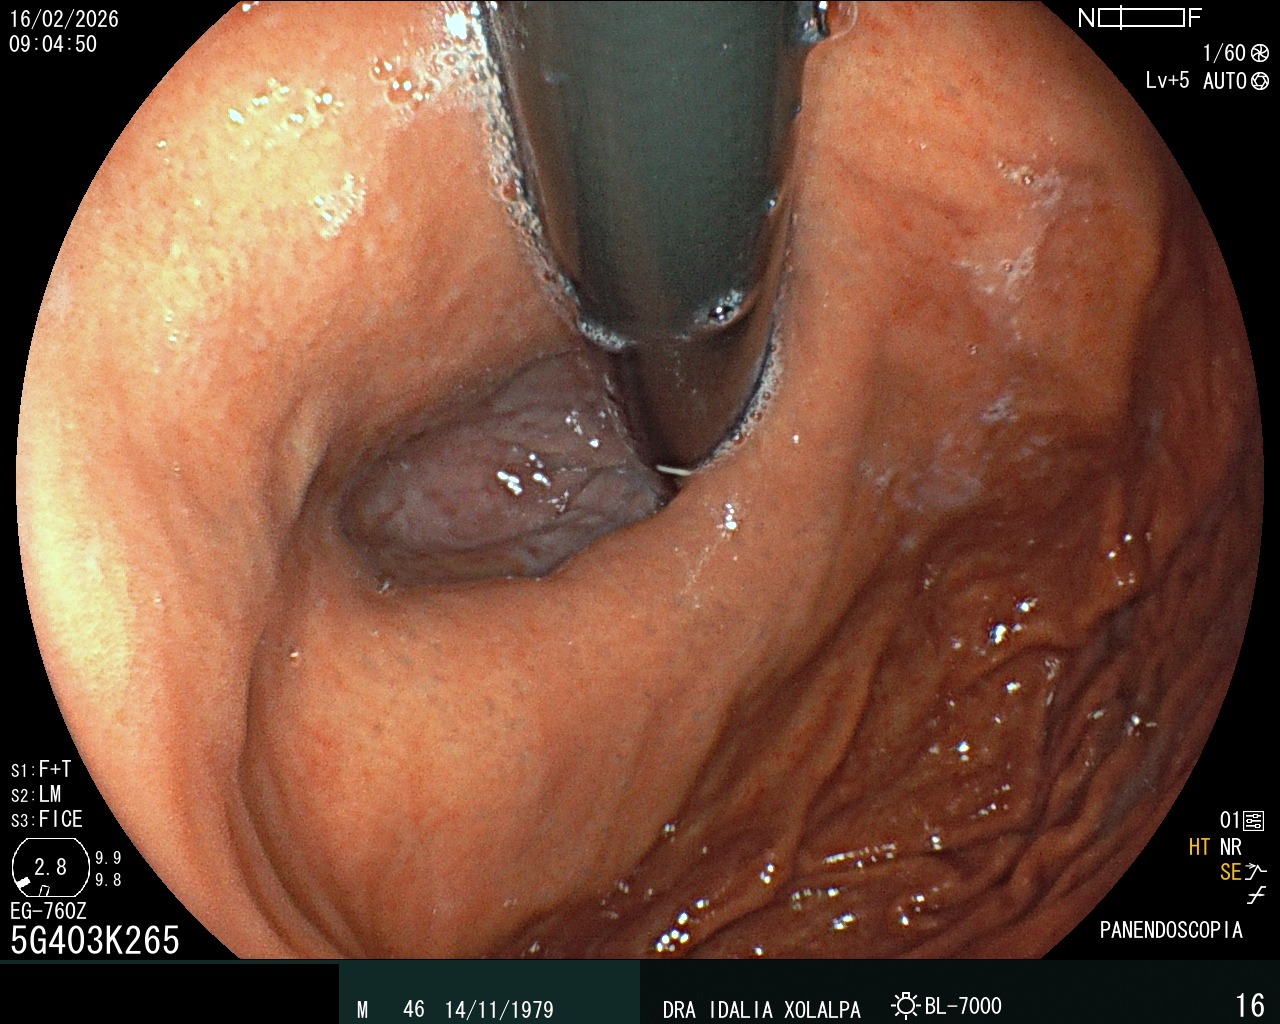

Hernia Hiatal

Identificación de hernia hiatal por endoscopia